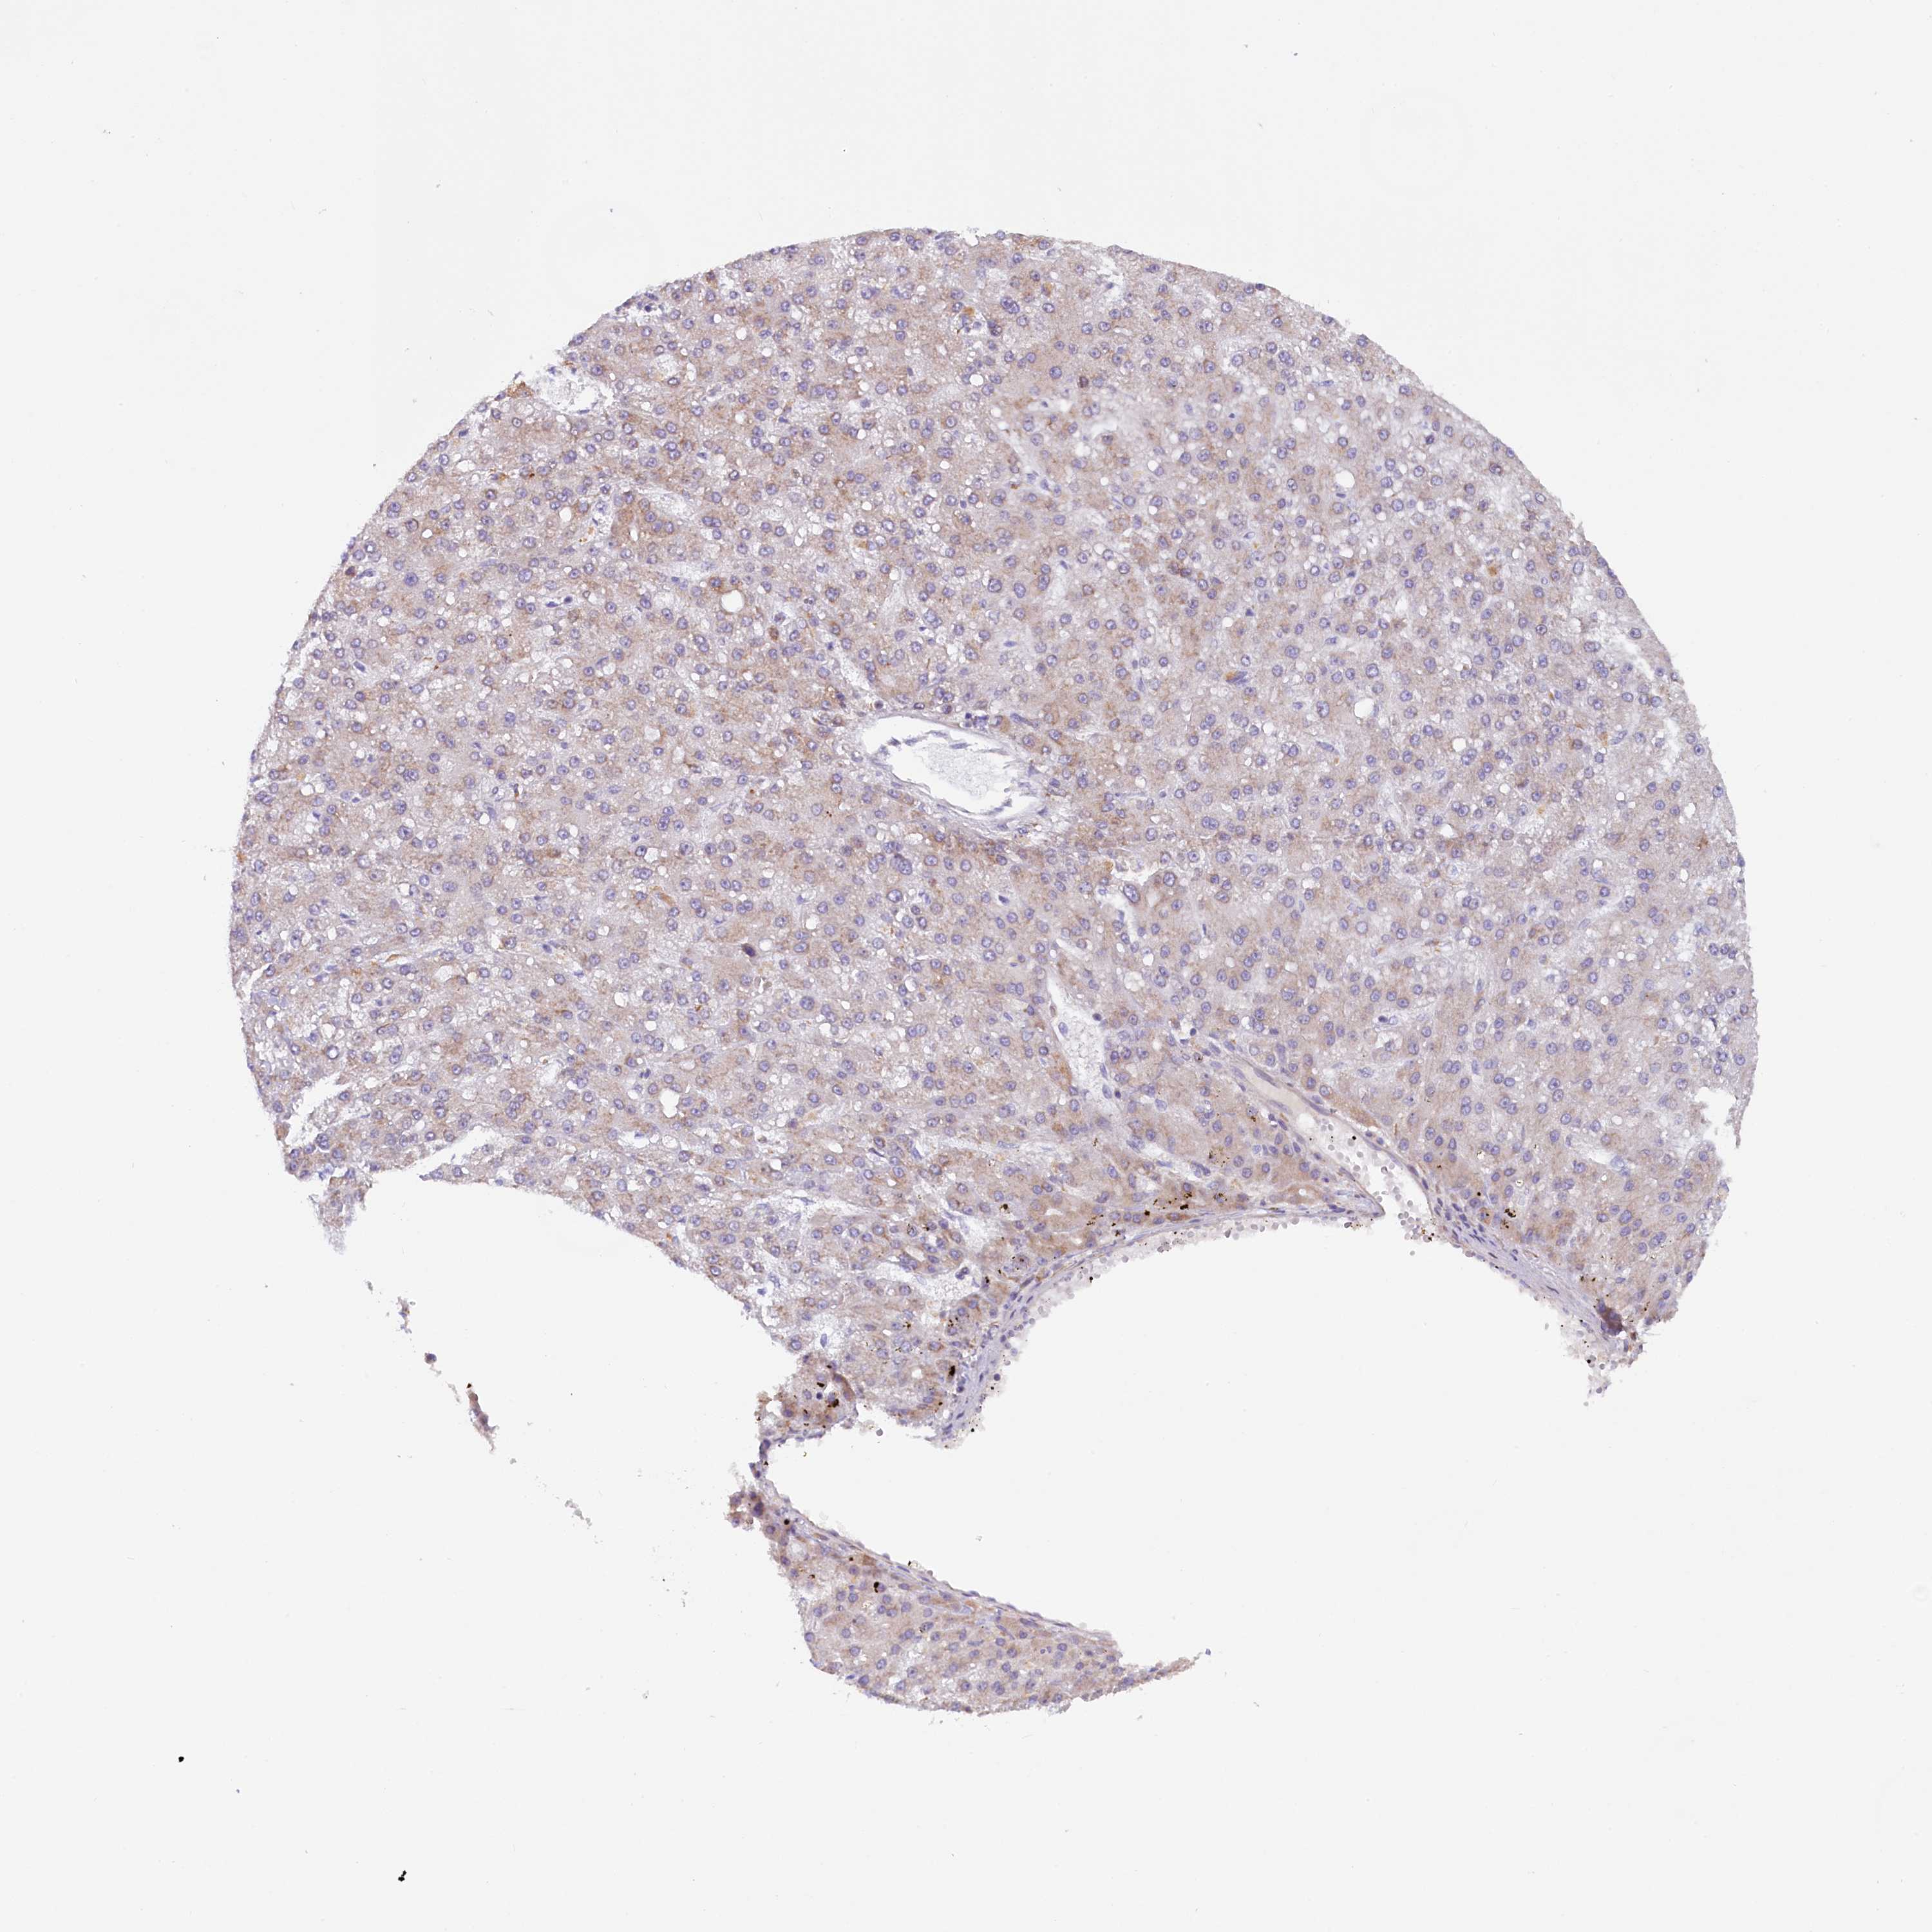

LIVER CANCER - Protein expressioni

A mouse-over function shows sample information and annotation data. Click on an image to view it in a full screen mode. Samples can be filtered based on level of antibody staining by selecting one or several of the following categories: high, medium, low and not detected. The assay and annotation is described here.

Note that samples used for immunohistochemistry by the Human Protein Atlas do not correspond to samples in the TCGA dataset.

Antibody stainingi

Antibody staining in the annotated cell types in the current human tissue is reported as not detected, low, medium, or high, based on conventional immunohistochemistry profiling in selected tissues. This score is based on the combination of the staining intensity and fraction of stained cells.

Each image is clickable and will lead to virtual microscopy that enables deeper exploration of all samples and also displays staining intensity scores, fraction scores and subcellular localization as well as patient and tissue information for each sample.

Antibody HPA042008

Staining

High

Medium

Low

Not detected

Intensity

Strong

Moderate

Weak

Negative

Quantity

>75%

75%-25%

<25%

None

Location

Nuclear

Cytoplasmic/membranous

Cytoplasmic/membranous,nuclear

Cholangiocarcinoma

Carcinoma, Hepatocellular, NOS